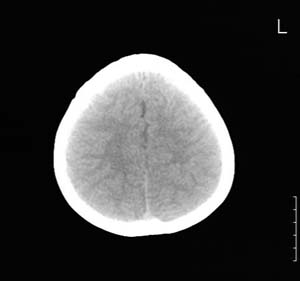

以下是引用lixi在2006-12-5 21:06:00的发言:[br]1、dandy-walker变异。2、胼胝体发育不良。

以下是引用zhuoshandiao在2006-12-5 21:41:00的发言:[br]胼胝体发育不良应该是肯定的。另外考虑dand-walker畸形。

以下是引用卜一在2006-12-5 22:30:00的发言:[br]支持考虑:1、dandy-walker变异。2、胼胝体发育不良